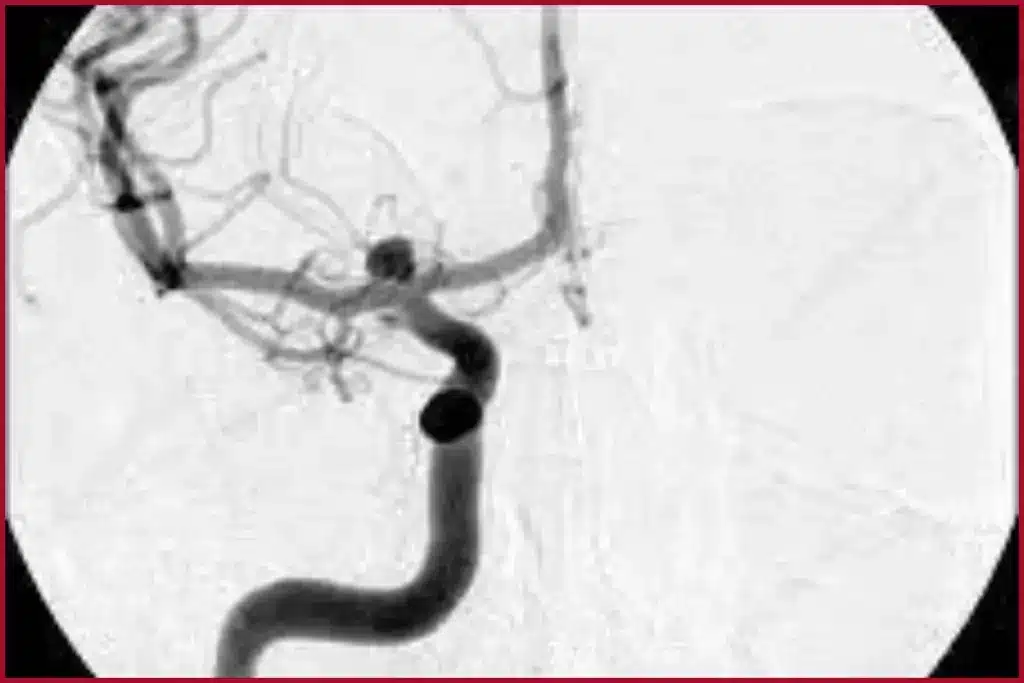

An angiogram lets doctors see inside blood vessels. They can spot blockages or other issues. This helps them plan the best treatment.

The main goal of an angiogram is to find and treat heart problems. It shows detailed pictures of blood vessels. This helps doctors spot blockages, aneurysms, or other issues.

Understanding the Images

To get what your angiogram results mean, you need to know about the images. Angiogram images show how your blood vessels are doing. They can spot blockages, narrow spots, or other issues. These images are key for finding vascular diseases and planning treatments.

Your doctor will look at your images for signs of disease. This includes stenosis (narrow arteries) or aneurysms (ballooning blood vessels). Knowing this helps make better choices for your care.

Angiograms are vital for finding heart diseases. They let doctors see inside blood vessels. This helps them spot blockages or problems that might be causing health issues.

Role in Identifying Blockages

Angiograms mainly help find blockages in the heart’s system. They show where blood vessels are narrowed or blocked. This info is key for deciding how to treat patients at risk of heart attack or stroke.